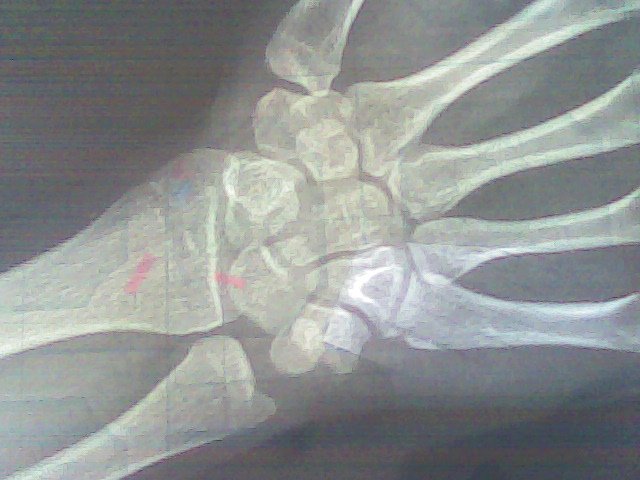

帮忙看一下骨龄片,女生,15岁,现身高153.5厘米,月经初潮13岁半 父母亲身高151cm,164cm.我能长多高? 我现在骨龄几岁?我还能长多高? 点击展开 匿名用户 2013-02-22 14:58 满意回答 差不多155cm,这个身高可以了。 势凌春_8KEC 2013-02-23 21:00 宝宝知道提示您:回答为网友贡献,仅供参考。 为您推荐: 其他回答 基本没有空间了,基本闭合了! 陶伶俐_I2Nz 2013-02-22 16:09 相关问题 我女儿12岁月经初潮,测骨龄是13岁,身高146 5厘米,还能长到多高啊? 重庆儿童医院网上挂号十月三十一日上午的,女:13岁,骨龄15岁,月经初潮两年多,身高1 46米,左 孩子身高偏矮,想去检测—下骨龄,请问该挂什么科